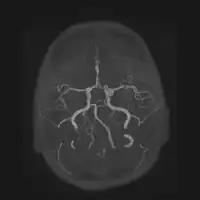

| Aneurysm of the basilar artery and the vertebral arteries. | |

Aneurysms in the posterior circulation (basilar, vertebral and posterior communicating artery) have a higher risk of rupture. Basilar artery aneurysms represent only 3–5% of all intracranial aneurysms but are the most common aneurysms in the posterior circulation.